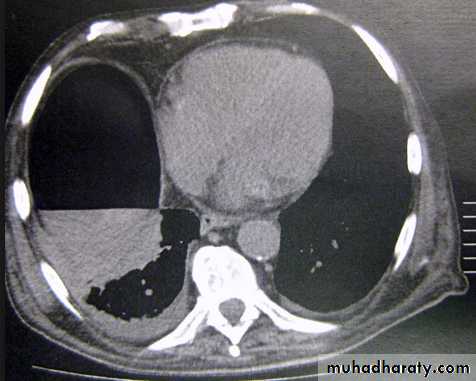

Massive pleural effusion with mediastinal shift to the left.

(A) Chest radiograph

(B) CT coronal reconstruction. A massive effusion displaces the mediastinum to the left. CT shows the important pleural effusion together with the enhanced atelectatic left lung.

Note also the depression of the right hemidiaphragm (arrows).